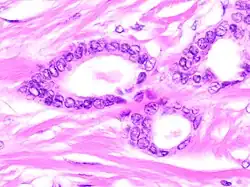

Histopathology of tubular carcinoma, low magnification, H&E stain. It shows the typical features of invasive breast cancer with infiltrative growth pattern, here including invasion into adipose tissue and with an associated fibrous or desmoplastic stromal response. It has the criterion of more than 90% of the tumor composed of small, ovoid or angulated tubules with open lumina. Ductal carcinoma in situ is seen at left as lumina with micropapillary formations (under the larger bland cyst), and was presumably the precursor lesion for the ductal carcinoma.[1]